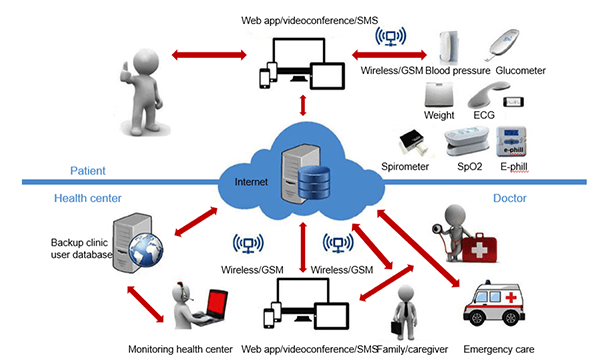

Wireless Body Area Network (WBAN)

Wireless Body Area Network (WBAN) is a technique used for remotely monitoring the patient’s health and gathering the related information from the embodied sensors. It consists of a small wireless network that contains several small devices, i.e. sensor nodes and actuators. The sensor nodes are placed directly either on the body or under the skin of a person to compute certain body parameters such as an electrocardiogram (ECG), electroencephalogram (EEG), body movement, temperature, blood pressure, blood glucose, and respirations.

PDA

A smartphone can remotely access the information sensed by the sensors or a Personal Digital Assistant (PDA) between the patient and a doctor, nurses, pharmacies who take sensitive decisions or actions depending on the information acquired from those sensors. These critical decisions and medical information must be protected against unauthorized access that could be dangerous to the life of the patient and sometimes lead to death, i.e. change of dosage of drugs or treatment procedures, if falls on the wrong hand. Thus, scalable and strict security mechanisms are mandatory and should include secure group management, confidentiality, privacy, integrity, authorization, and authentication.